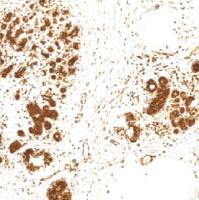

CD16是种低亲和力的Fc受体,主要存在于自然杀伤细胞的表面嗜中性粒细胞多形核白细胞、单核细胞和巨噬细胞中。在免疫组化染色技术中,CD16可从外周T细胞淋巴瘤中鉴别诊断出v6T细胞淋巴瘤和v6T细胞大颗粒淋巴细胞性白血病。据报道,结直肠癌患者高CD16阳性细胞浸润表达与改善整体的存活率有一定的关系。

- 阳性部位:胞质,胞膜

- 适用组织:石蜡切片

- 预处理:热修复